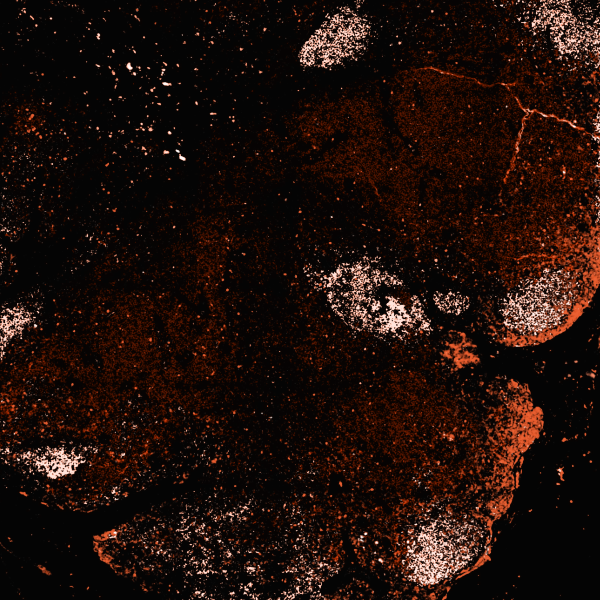

Hematological Disorders

Basophilia signals immune activation or myeloproliferative activity; measuring basophils—especially the absolute basophil count—clarifies allergic, inflammatory, or hematologic drivers. At Superpower, we provide Basophils and Absolute Basophils blood tests for basophilia, in-clinic and at-home. Home blood testing is available in selected states. (See FAQs below for more info).

Blood testing is essential for diagnosing and monitoring disseminated intravascular coagulation (DIC), a life‑threatening clotting disorder. At Superpower, we provide Platelets, WBC, and CRP testing for DIC. We offer in‑clinic and at‑home blood testing; home testing is available in selected states. (See FAQs below for more info).

Blood testing for eosinophilia clarifies immune activation that drives allergies, asthma, parasitic infection, and other inflammation. At Superpower, we measure Eosinophils and Absolute Eosinophils to assess granulocyte burden. We offer in-clinic and at-home testing; home collection is available in selected states. (See FAQs below for more info).

Blood testing clarifies red blood cell turnover and destruction (hemolysis), guiding diagnosis and severity. At Superpower, we test Hemoglobin, RDW/MCV Ratio, Bilirubin Indirect, and BAR for Hemolytic Anemia. Superpower offers in-clinic and at-home testing; home collection is currently available in selected states. (See FAQs below for more info).

Blood testing is vital for early detection and monitoring of leukemia, revealing marrow and immune system activity. At Superpower, we test WBC, Neutrophils, Lymphocytes, Monocytes, and RDW. We offer in-clinic and at-home testing; home testing is available in selected states. (See FAQs below for more info).